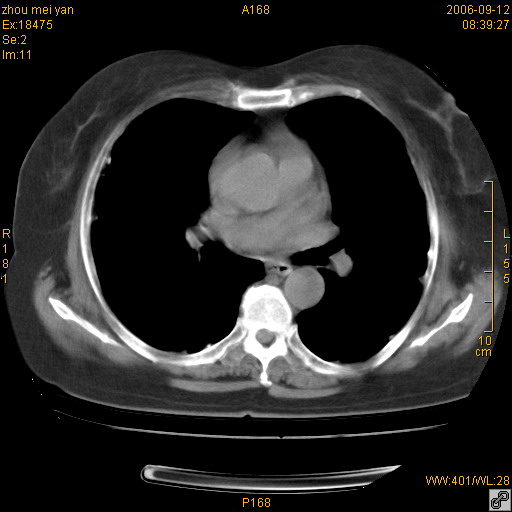

患者、女、55岁。因心率失常住院检查ct发现胸部多发结节。腹部b超肝、胆、胰、脾、肾、子宫附件未见异常。无结核病史,无粉尘接触史。请大家来会诊。谢谢!

病变位于胸膜,多发结节,边界清楚,内见小结节状钙化。其它未见异常。

双侧胸膜多发结节,形态不规则,边缘较清楚,每一个结节中心似乎都有钙化点的特征,与胸膜广基相切。临床无结核病史,无粉尘接触史。

胸膜间皮瘤可能性大。在气管隆突前可见一肿大淋巴结影。

考虑恶性胸膜间皮瘤可能性大,病灶位于胸膜,以宽基地与胸膜相连,呈结节样改变,部分病灶内可见点状钙化影。请各位老师多多指导!

我认为该病例不考虑是1:胸膜间皮瘤{1,胸膜的增生分布范围较广。2,其内有钙化,在胸膜间皮瘤中钙化的发生很少}。2:结核性胸膜炎后遗症也不考虑{结核性胸膜炎一般都会引起胸腔的积叶和临近肺实质的改变}。